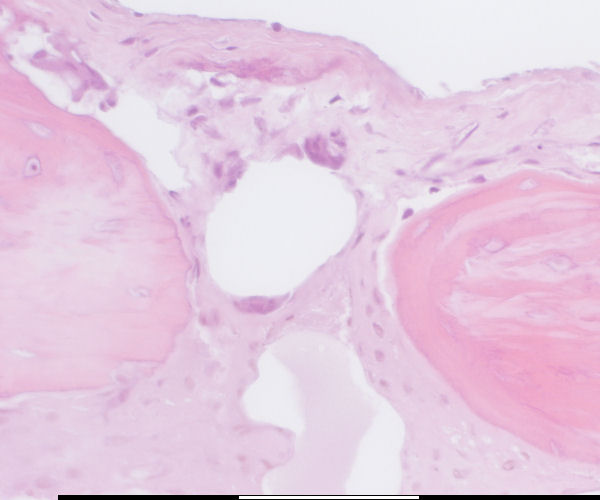

back Osteoclast progenitor cells